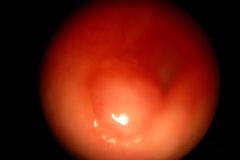

Tympanic Membrane

Ear Canal